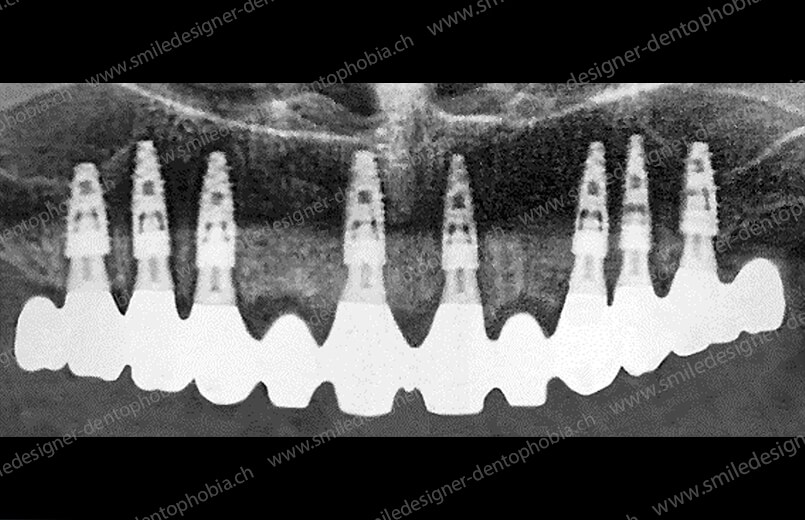

Cas clinique « GOLD DAMAGE CONTROL MCI » maxillaire : Bridge implanto-porté avec extensions postérieures (ALL ON 10). Version définitive des bridges avec un cosmétique en céramique.